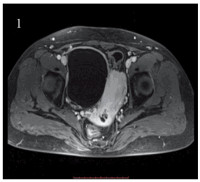

Competing interests: The authors declare that they have no competing interests.作者贡献:王立娟: 论文撰写邹凌凤: 提供病例郭小红: 论文指导曹晓静: 图片制作王军大: 提供影像学图片曾敏: 文章审校 -